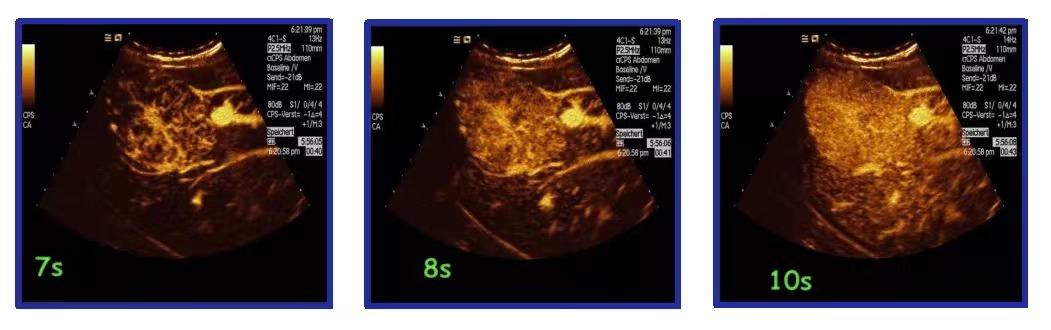

穿刺活检进行病理学检查是肿瘤诊断的“金标准”。为精确诊断,超声医学科秦川主任对患者进行肿块穿刺活检,因肿块达20cm,为提高穿刺取材的准确性,秦川主任术前利用超声造影技术,以往传统穿刺可能因为术前未能定位肿瘤,需要多次穿刺,此次秦川主任术前利用的超声造影技术定位精准,精确导航肿瘤位置,一次穿刺成功,减少患者疼痛感,提高病理诊断准确性。此外超声造影对血管的显示优势明显,造影辅助,明显降低血管的损伤,减少术中出血量。术后刘奶奶无明显不适,无明显出血。